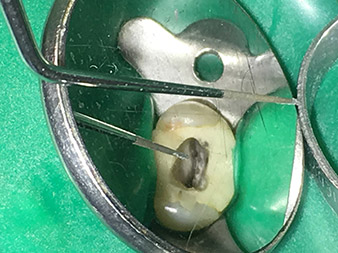

Dr. Nouraie: I particularly enjoy working with the 1E tip. It is perfectly suited to activating the rinsing fluid in the root canal system. The delicate design of the tip allows you to reach deep sections of the canal too and ensure optimal activation.

Thanks to the material reinforcement at the transition from the working end to the shaft, the risk of this thin instrument breaking has now been minimized.

Dr. Nouraie: I have various favourite tips, but my absolute favourite tip and the one I couldn’t be without is the 1E tip. It really is useful in every single root canal treatment, as it can be used to activate the rinsing fluid. It is well known that, alongside the preparation, rinsing of the root canal is the most important component of the treatment. Activated rinsing fluid penetrates deeper into the dentinal tubules, thereby achieving better results. As such, activation of the rinsing fluid plays an important role in improving the quality of this type of treatment.

Pictures: Dr. Shahrad Nouraie Ashtiani, Bremen